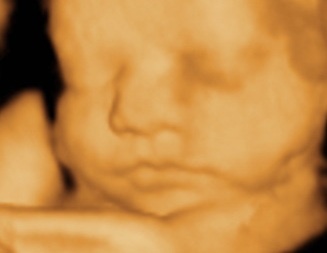

Si tu si bebelusul sunteti pregatiti sa va intalniti. Imparte bucuria, nerabdarea si emotiile cu tatal copilului tau. Este la fel de implicat si de nerabdator ca si tine.

Cei care se afla in jurul tau sunt acolo doar pentru a te sustine, ajuta si proteja. Insa tu esti cea care aduce copilul pe lume.